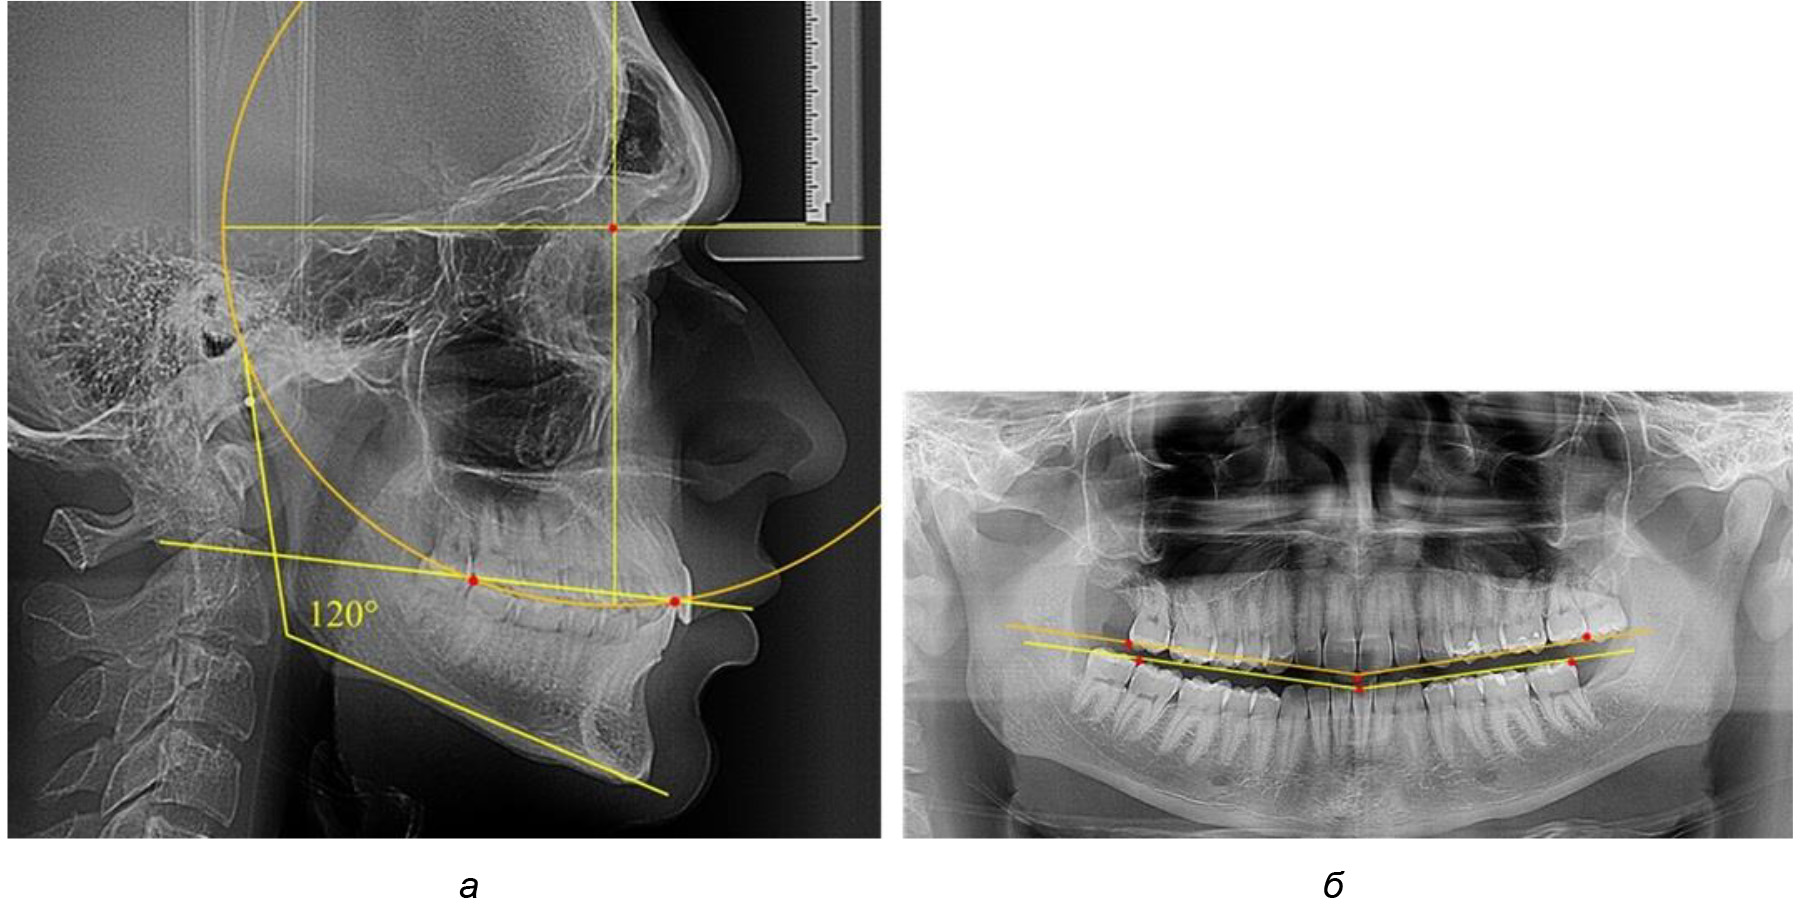

После лечения пациентов техникой «прямой» дуги, так же как и в 1-й подгруппе, было отмечено увеличение сагиттального размера окклюзионной лини в среднем на (2,38 ± 0,83) мм. Окклюзионная линия практически касалась окклюзионного контура всех жевательных зубов, и отмечалось практически полное отсутствие кривой Spee, так же как и у людей 1-й подгруппы 2-й группы (рис. 6).

Рис. 6. Особенности ТРГ при оптимальной кривой Spee до лечения (а) и после лечения (б) техникой «прямой» дуги

Таким образом, проведенное лечение техникой «прямой» дуги способствует нормализации окклюзионного равновесия и торку передних зубов, однако не соответствует оптимальному окклюзионному статусу, характеризующему физиологическую окклюзию. При этом величина нижнечелюстного угла оставалась на прежнем уровне.